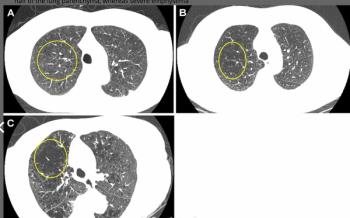

A deep learning AI platform, which incorporated radiomic features including CT attenuation metrics, demonstrated a 93.6 percent AUC for detecting invasive adenocarcinoma on chest CT.